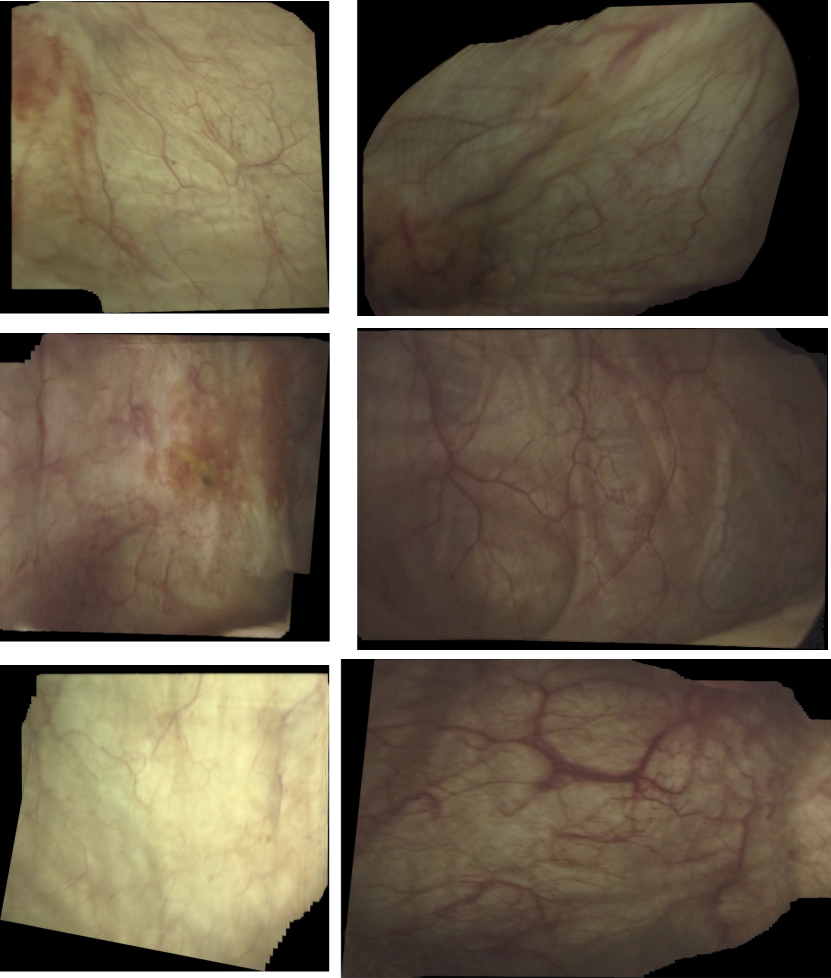

Full clinical endoscopic videos taken for 21 patients were used for our experiments. Figure 3 shows few frame samples from the dataset. In all of the conducted experiments, we randomly selected 16 video sequences to generate our training data and the remaining 5 video sequences for validation in a cross-validation scheme. In addition, we repeated all experiments 5 times with different random splits in a cross-validation scheme.

Figure 3: Samples of clinical endoscopic images taken from different patients.